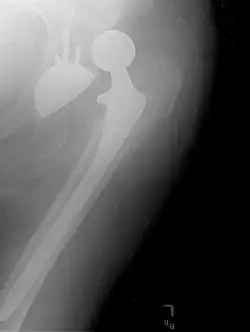

Dislocated artificial hip

Liner wear, particularly when over 2 mm, increases the risk of dislocation.[15] Liner creep, on the other hand, is normal remoulding.[16]

Dislocation (the ball coming out of the socket) is one of the most common complications. Hip prosthesis dislocation mostly occurs in the first three months after insertion, mainly because of incomplete scar formation and relaxed soft tissues.[15] The chance of this is diminished if less tissue is cut, if the cut tissue is repaired and if large diameter head balls are used.[17] Surgeons who perform more operations tend to have fewer dislocations. Important factors which are related to dislocation are: component positioning, preservation of the gluteal muscles and restoration of leg length and femoral offset.[18] Keeping the leg out of certain positions during the first few months after surgery further reduces risk.